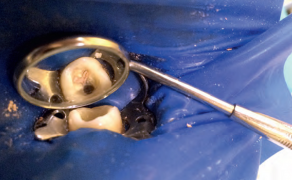

STRESZCZENIE: Endodoncja to dziedzina stomatologii stanowiąca każdego dnia wyzwanie dla wielu stomatologów. Aby efekt końcowy leczenia okazał się sukcesem, potrzebne będą narzędzia i metody, które pozwolą go osiągnąć. Nowoczesna endodoncja posiłkuje się wieloma etapami pracy, przyrządami i narzędziami. Dlatego niezwykle istotne jest również doświadczenie kliniczne i wyczucie stomatologa. Wybór mogą znacznie ułatwić narzędzia, które pozwalają na minimalnie inwazyjną, ale również maksymalnie skuteczną pracę w kanale. Materiałem, z którego powinny być wykonane takie narzędzia, jest stop niklowo-tytanowy (Ni-Ti). Przykładem może być np. ZenFlex firmy Kerr. Metoda opracowania kanałów korzeniowych powinna być dobrana indywidulnie do zęba pacjenta. Morfologia systemów kanałowych bywa bardzo różnorodna, a istnieją również miejsca konieczne do oczyszczenia, do których nie docierają narzędzia. Dzięki dobraniu odpowiednich substancji płuczących możliwe jest ich właściwe oczyszczenie. Jako przykład przedstawione zostały dwa przypadki kliniczne leczenia zęba 21 oraz 16.